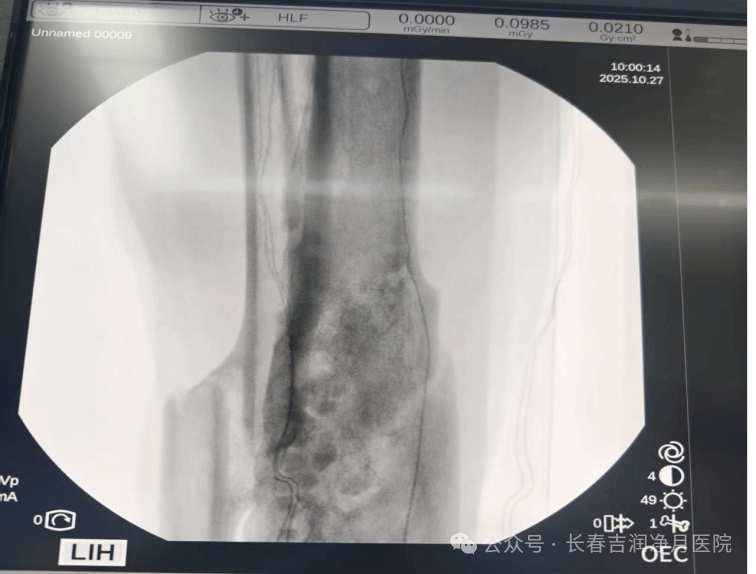

2025年10月,张先生入住我院接受决定性治疗。于铁成主任团队经过充分准备,为患者实施第二阶段手术。术中通过精准操作,完整取出抗生素链珠,彻底清创后植入抗生素硫酸钙骨粉。手术过程顺利,耗时短,创伤小。

术后随访显示,骨折愈合良好,感染指标完全正常,患肢已恢复正常功能。

(2025年10月,第二次手术术中胫腓骨正侧位)